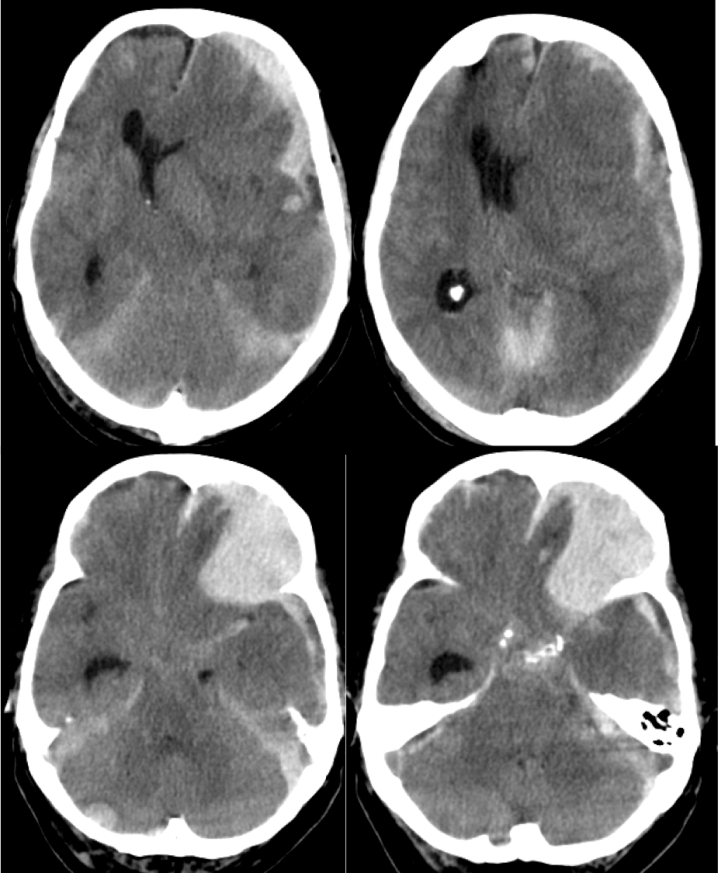

Transtentorial: puede ser unilateral/uncal o bilateral/central.

- Por descenso del contenido supratentorial a través de la tienda del cerebelo.

- Puede ser unilateral o Uncal = descenso del uncus hacia el interior de la cisterna supraselar.

- Dilatación del asta lateral contraletaral

- Dilatación de la cisterna ambiens y prepontina ipsilateral.

- Bilateral o Central = obliteración las cisternas basales

- Hay riesgo de infartos por compresión la ACP y perforantes.

- Pueden producir hemorragias de Duret (mesencéfalo) o de Kreonhan (pedúnculo cerebral contralateral)

Trasntentorial ascendente:

- Por ascenso de estructuras.

- Se produce desplazamiento del mesencéfalo y borramiento de cisuras.